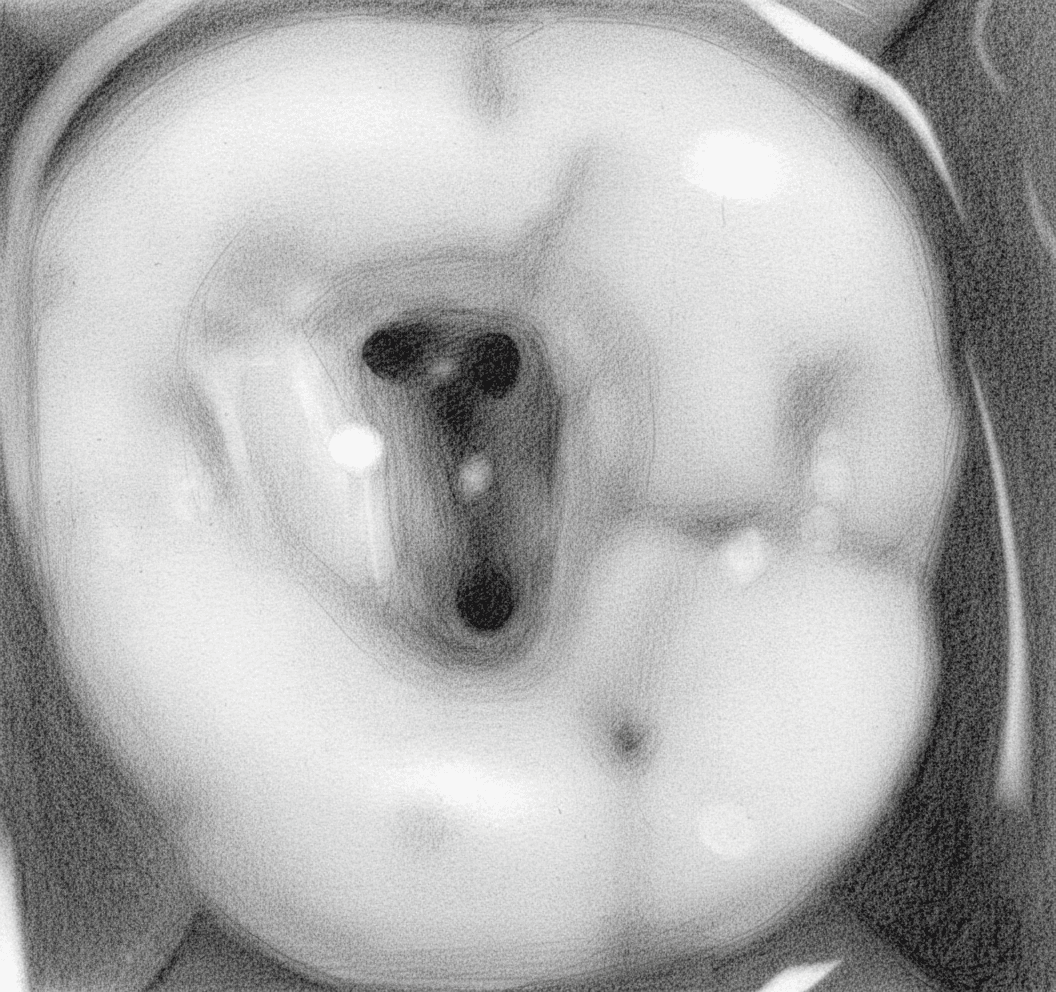

Maxillary Second Molar - Axial View showing triangular access with closely spaced canal orifices

Access smaller than first molar — canal orifices much closer together; risk of gouging between canals

Restricted access due to posterior position — longer burs and good mouth opening essential